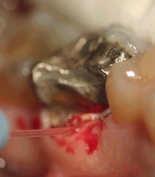

Surgery with Laser since the prosthetic edge

At this treatment and setting, one work with Anestesie. The anaemic working, allow us a very good view to be able to prepare a perfect tooth stump.